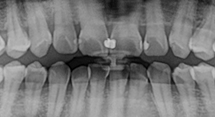

歯と口の中の状態を正確に把握するためにデジタルパノラマレントゲンや口腔内カメラなどを完備しております。

レントゲンなどで表面からは見えない治療箇所も把握できますので、正確で無駄のない治療を行えます。